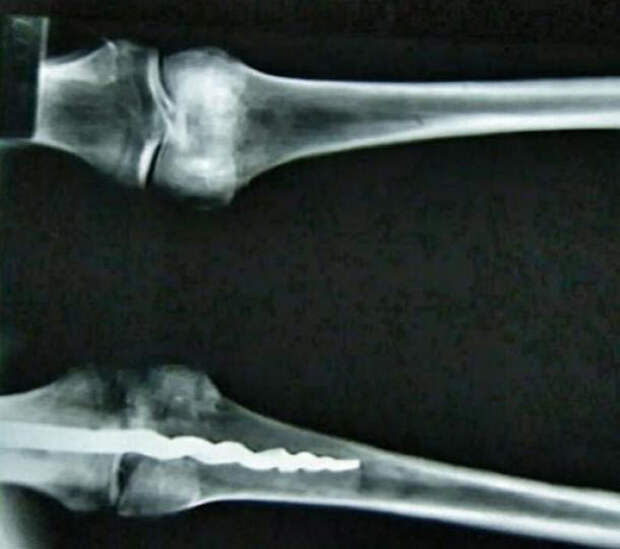

В левом колене мумии обнаружили ортопедический штифт длиной 23 см сделанный из металла. Он был вживлен благодаря таким сложнейшим биомеханическим принципам, которые не уступают даже самым современным технологиям.

Группа ученых обнаружила следы древней органической резины, похожей на современный клей для костей, а также следы древних жиров и волокон тканей, которые, благодаря этой резине, все еще были прочно зафиксированы на месте. Дополнительные исследования показали, что медицинская процедура высокого уровня была проведена в древние времена, приблизительно 2600 лет назад.

Группа исследователей была поражена тем, что штифт был спроектирован по тем же принципам, которые используют в современном мире для фиксации костей.

«Мы восхищаемся тем, что в древнем Египте сумели создать штифт согласно тем биомеханическим принципам, которые мы все еще используем сегодня, как например при жесткой фиксации кости, – говорит доктор Ричард Джексон, – это превзошло все наши ожидания».

Представители университета Бригама Янга сообщают, что у штифта «острый крюкообразный конец для лучшего вживления в бедренную кость – точно такие же биомеханические методы используются в наши дни. Другой конец штифта, расположенный в берцовой кости, имеет три «зубчика», которые предотвращают смещение положения штифта в кости».